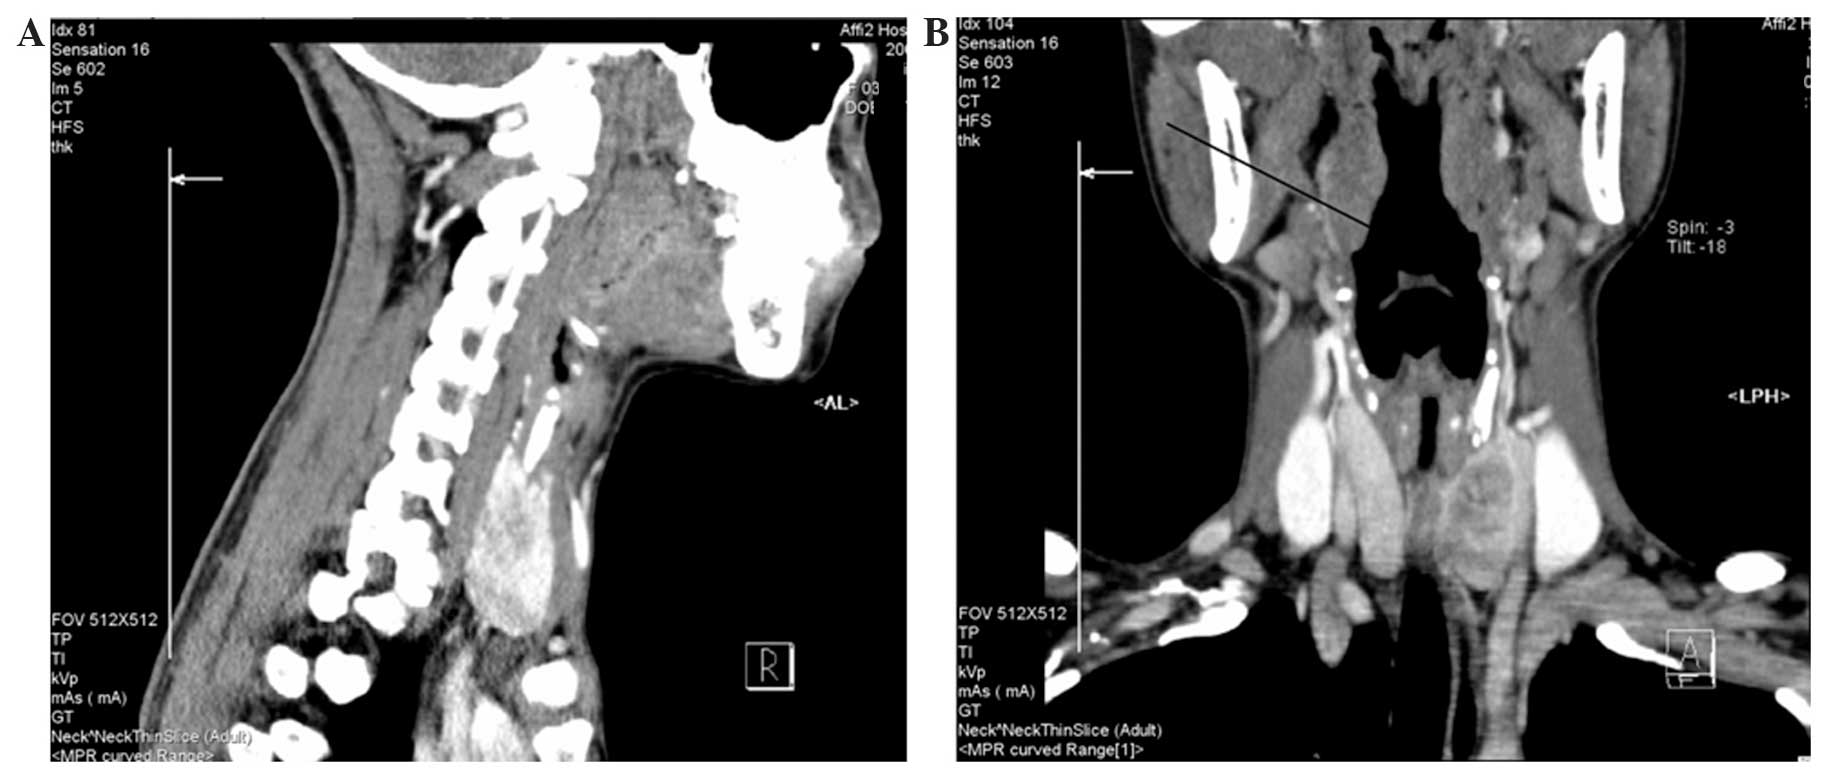

Locally Advanced Asymptomatic Papillary Thyroid Cancer Presenting With Retropharyngeal Lymph Node Metastasis Symptoms Kholmatov Gland Surgery

gs.amegroups.com